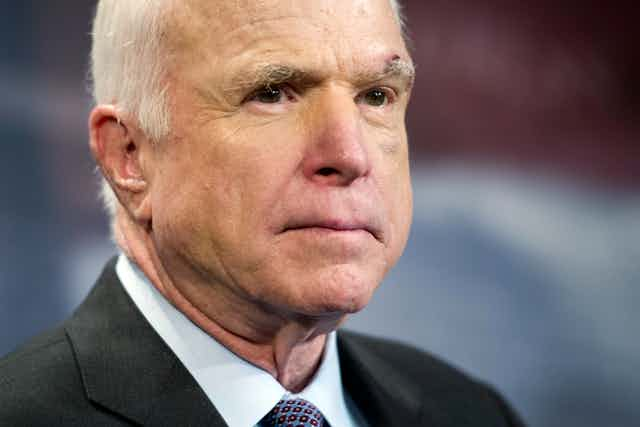

Sen. John McCain withstood beatings and torture as a prisoner of war, but he was confronted with an enemy in July 2017 that he was ultimately unable to overcome. An aggressive and deadly brain cancer known as glioblastoma, or GBM, took McCain’s life on Aug. 25, 2018.

The man noted for his unstoppable resilience, pervasive optimism and uncompromising personal ethos was not able to conjoin forces with the marvels of modern medicine and defeat the insidious enemy of brain cancer.

Why is GBM so deadly? Why have so many individuals, with presumably all the physical and financial resources that can be amassed readily available to them, been unable to conquer this dreadful enemy? Sen. Edward M. Kennedy died from the disease exactly nine years earlier. In 2015, GBM also claimed the life of Joseph “Beau” Biden III, son of Joe Biden, the former vice president. It kills about 15,000 people in the U.S. each year. Most people diagnosed with the disease survive less than two years.

I am a physician and scientist who studies ways to stop GBM. Despite the sadness and great loss we feel at Senator McCain’s passing, we are making progress in the treatment of this disease.

Sen. McCain will be remembered for his many contributions, accomplishments and sacrifices in service of his country. He is also but one of the 600,000 Americans and 8.2 million people worldwide whose life will be claimed by cancer this year. Among the many things to be remembered, honored and cherished about his life, let the fighting legacy of this warrior remind us that war on cancer goes forward in his memory, and in honor of all that have been and will be impacted by this disease.